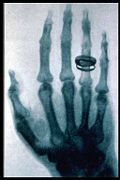

- January 5 - An Austrian newspaper reports that Wilhelm Röntgen discovered a type of radiation later known as X-rays.

- January 12 - H.L. Smith takes the first X-ray photograph.

- January 18 - The X-ray machine is exhibited for the first time.